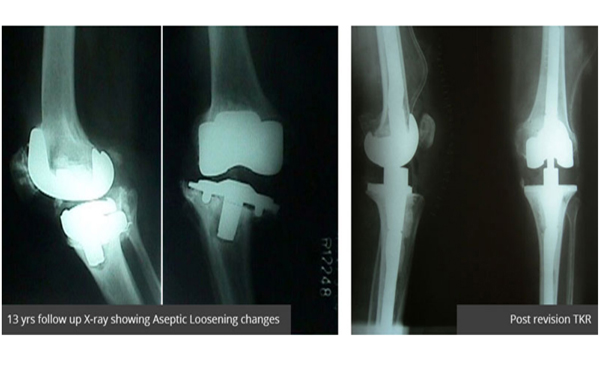

Revision Knee Replacement—A perfectly well-done knee Replacement may get infected or Instability may persist post knee replacement-these situations besides others may require a re do or revision knee replacement which increases patient morbidity and risks mortality too. Revision knee implants are more expensive and the procedure may involve 2 stages rather than a single stage surgery. The success rate of revision knee replacements is now approaching that of Primary knee replacement with availability of better implants and evolution of new techniques.